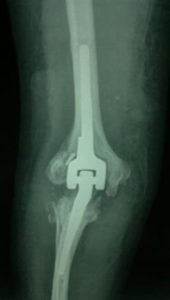

1. Eklem Protezleri: Omuz, dirsek veya bilek protezi takılarak hareket kabiliyeti artırılır.